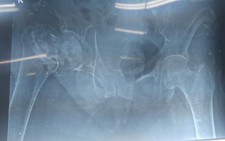

Các nhà nghiên cứu đã tìm kiếm chất chỉ dấu cho các tế bào Lympho T trong máu (được sản xuất ở tuyến ức, một tuyến ở ngực, tuyến này thường bị thoái hóa khi trưởng thành) có chức năng giúp hệ miễn dịch phản ứng lại các bệnh nhiễm trùng mới.

Họ phát hiện, cơ thể những người đạp xe đạp đường dài đã sản xuất ra lượng tế bào Lympho T tương đương những người ở độ tuổi 20. Ở những người lớn tuổi không vận động, các tế bào này chỉ được sản xuất với số lượng rất ít.